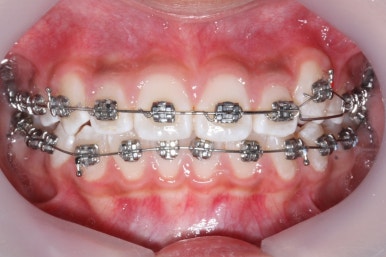

장치를 부착한 후에 순차적으로 변화가 나타나는 모습입니다.

총 4장의 사진 동안 경과한 시간은 불과 6개월 입니다. 헤드기어를 통해 사전에 작업을 해뒀기 때문에 이후 연산동덧니교정 과정은 편해진 것이죠.

윗니만 6개월이 지난 모습입니다.

치열이 매우 가지런해졌죠. 이 후에는 특이사항 없이 종료가 되었습니다.

연산동덧니교정을 하고자 키다리아저씨치과에 처음 내원했을 때와 개선이 된 후의 비교 모습입니다. 영구치가 모두 나왔고 덧니가 개선이 된 후에 마무리가 되었습니다.